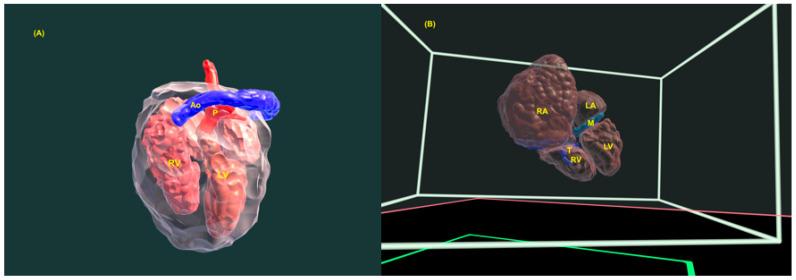

Congenital heart defects (CHDs) are the most common congenital defect, occurring in approximately 1 in 100 live births and being a leading cause of perinatal morbidity and mortality. Of note, approximately 25% of these defects are classified as critical, requiring immediate postnatal care by pediatric cardiology and neonatal cardiac surgery teams. Consequently, early and accurate diagnosis of CHD is key to proper prenatal and postnatal monitoring in a tertiary care setting. In this scenario, fetal echocardiography is considered the gold standard imaging ultrasound method for the diagnosis of CHD. However, the availability of this examination in clinical practice remains limited due to the need for a qualified specialist in pediatric cardiology. Moreover, in light of the relatively low prevalence of CHD among at-risk populations (approximately 10%), ultrasound cardiac screening for potential cardiac anomalies during routine second-trimester obstetric ultrasound scans represents a pivotal aspect of diagnosing CHD. In order to maximize the accuracy of CHD diagnoses, the views of the ventricular outflow tract and the superior mediastinum were added to the four-chamber view of the fetal heart for routine ultrasound screening according to international guidelines. In this context, four-dimensional spatio-temporal image correlation software (STIC) was developed in the early 2000s. Some of the advantages of STIC in fetal cardiac evaluation include the enrichment of anatomical details of fetal cardiac images in the absence of the pregnant woman and the ability to send volumes for analysis by an expert in fetal cardiology by an internet link. Sequentially, new technologies have been developed, such as fetal intelligent navigation echocardiography (FINE), also known as "5D heart", in which the nine fetal cardiac views recommended during a fetal echocardiogram are automatically generated from the acquisition of a cardiac volume. Furthermore, artificial intelligence (AI) has recently emerged as a promising technological innovation, offering the potential to warn of possible cardiac anomalies and thus increase the ability of non-cardiology specialists to diagnose CHD. In the early 2010s, the advent of 3D reconstruction software combined with high-definition printers enabled the virtual and 3D physical reconstruction of the fetal heart. The 3D physical models may improve parental counseling of fetal CHD, maternal-fetal interaction in cases of blind pregnant women, and interactive discussions among multidisciplinary health teams. In addition, the 3D physical and virtual models can be an useful tool for teaching cardiovascular anatomy and to optimize surgical planning, enabling simulation rooms for surgical procedures. Therefore, in this review, the authors discuss advanced image technologies that may optimize prenatal diagnoses of CHDs.

先天性心脏病(CHD)是最常见的先天性缺陷,约每100例活产中就有1例发生,是围产期发病和死亡的主要原因。值得注意的是,这些缺陷中约25%被归类为重症,需要儿科心脏病学和新生儿心脏外科团队在出生后立即进行护理。因此,在三级医疗环境中,早期准确诊断CHD是进行适当产前和产后监测的关键。在这种情况下,胎儿超声心动图被认为是诊断CHD的金标准成像超声方法。然而,由于需要合格的儿科心脏病学专家,这种检查在临床实践中的可用性仍然有限。此外,鉴于高危人群中CHD的患病率相对较低(约10%),在常规孕中期产科超声扫描期间对潜在心脏异常进行超声心脏筛查是诊断CHD的一个关键方面。为了最大限度地提高CHD诊断的准确性,根据国际指南,在胎儿心脏的四腔心视图中增加了心室流出道和上纵隔的视图用于常规超声筛查。在这种背景下,四维时空图像相关软件(STIC)于21世纪初开发。STIC在胎儿心脏评估中的一些优点包括在孕妇不在场的情况下丰富胎儿心脏图像的解剖细节,以及能够通过互联网链接将容积发送给胎儿心脏病学专家进行分析。随后,开发了新技术,如胎儿智能导航超声心动图(FINE),也称为“5D心脏”,其中在胎儿超声心动图检查期间推荐的九个胎儿心脏视图是从心脏容积采集中自动生成的。此外,人工智能(AI)最近作为一种有前途的技术创新出现,有可能警告可能的心脏异常,从而提高非心脏病学专家诊断CHD的能力。在21世纪10年代初,3D重建软件与高清打印机的出现使得胎儿心脏的虚拟和3D实体重建成为可能。3D实体模型可以改善对胎儿CHD的家长咨询、盲孕孕妇的母婴互动以及多学科医疗团队之间的互动讨论。此外,3D实体和虚拟模型可以成为教授心血管解剖学和优化手术规划的有用工具,为手术操作提供模拟室。因此,在本综述中,作者讨论了可能优化CHD产前诊断的先进图像技术。